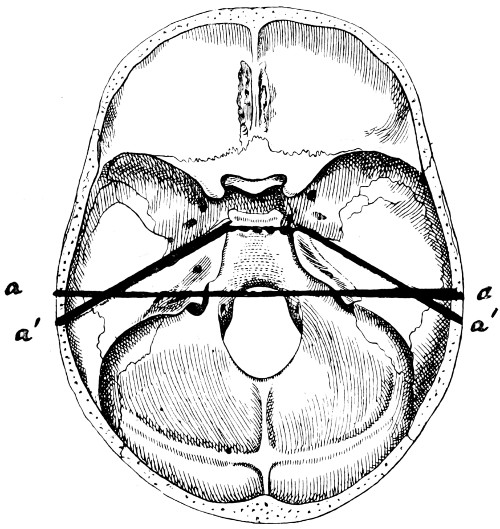

29 A and B. The base of the skull and the base as seen on transillumination 70, 71

30. Plan of the base of the skull 77